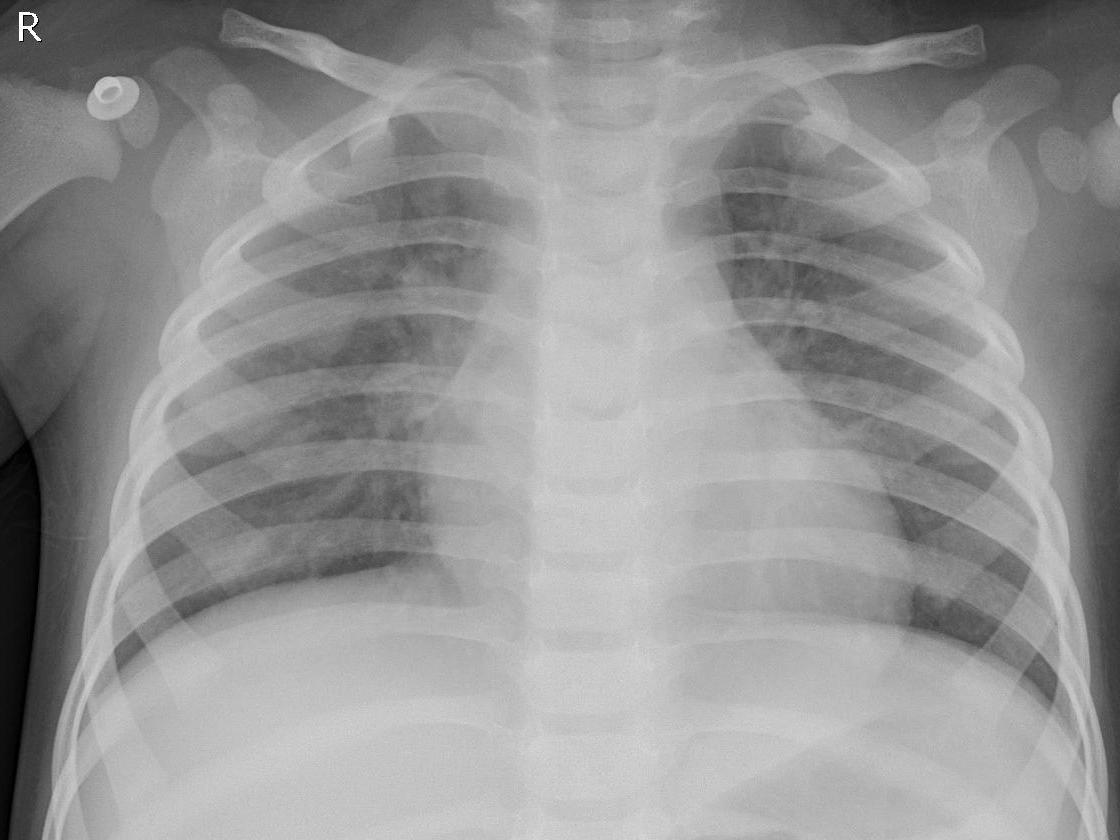

This dataset comprises 5,856 CXR images, divided into three categories: Normal, Bacterial Pneumonia, and Viral Pneumonia. For the purpose of this study, we frame the problem as a two-class classification task distinguishing between a healthy person (Normal) and one having any type of pneumonia (Pneumonia). This choice aligns with previous studies in this field [singh2023pneumonia, ayan2022diagnosis, szepesi2022detection]. The sample images from each class are shown in Figure 2.